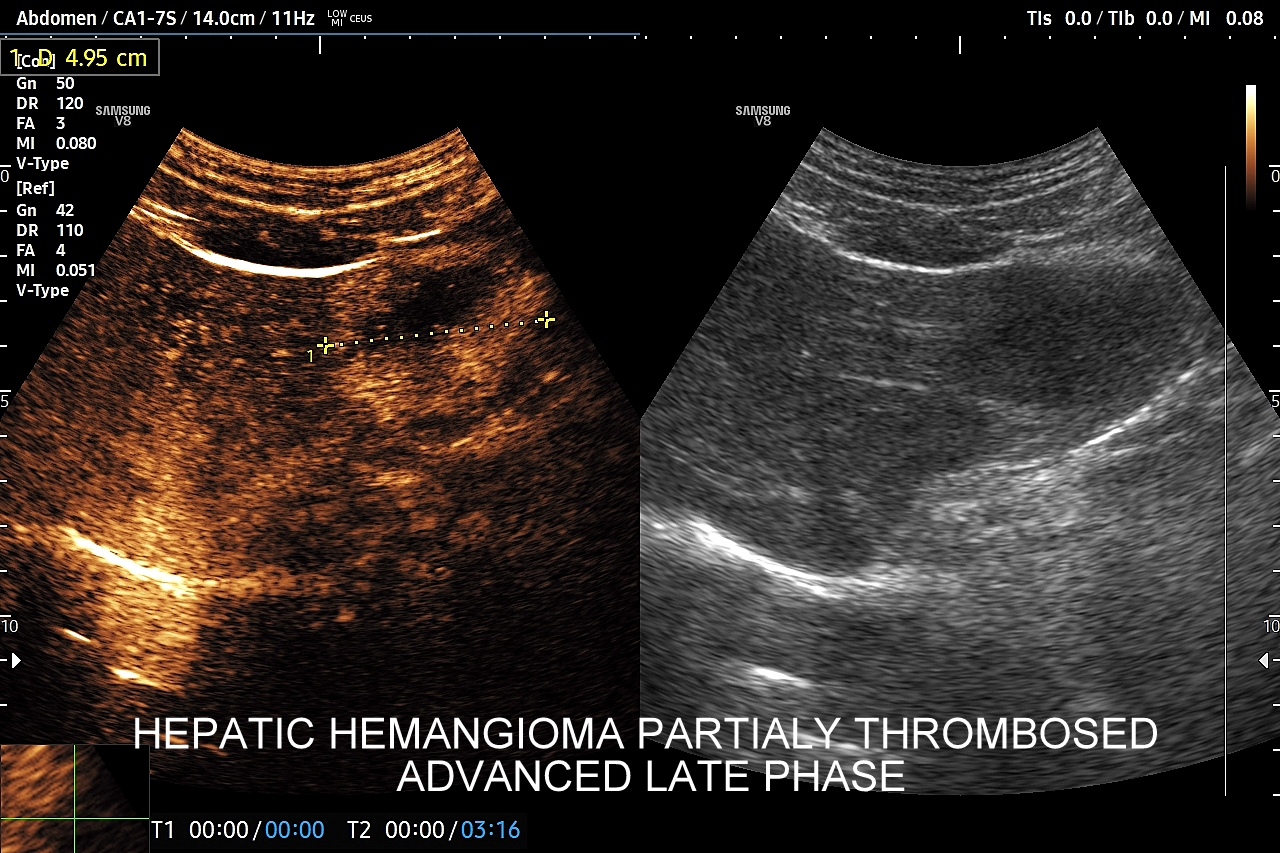

Najbardziej charakterystyczną cechą naczyniaka wątroby w badaniu CEUS jest jego wypełnianie w postaci guzkowej (ang. peripheral nodular enhancement) od obwodu ku centrum zmiany (ang. centripetal). Szybkość wypełniania bywa różnorodna, może być powolna lub szybka. W przypadku szybkiego wypełniania (tzw. flash-filling), w celu wykazania charakterystycznego centrypetalnego wypełniania niezbędna może być postprocessing’owa analiza poklatkowa zapisanego nagrania badania. W fazie późnej naczyniak wątroby pozostaje izowzmocniony lub hyperwzmocniony w stosunku do natywnego miąższu wątroby.

W przypadku dużych naczyniaków obszary, które uległy wykrzepianiu pozostają awaskularne przez wszystkie fazy badania CEUS, tj. nie wypełniają się kontrastem (nonenhancing). W przeciwieństwie do powyższego konstelacja, w której to w fazie wczesnej pojawia się wzmocnienie, a następnie w fazie wrotnej lub późnej ulega wypłukaniu (hypoenhancement) świadczy o cechach złośliwych diagnozowanej zmiany ogniskowej w wątrobie i wyklucza rozpoznanie naczyniaka.